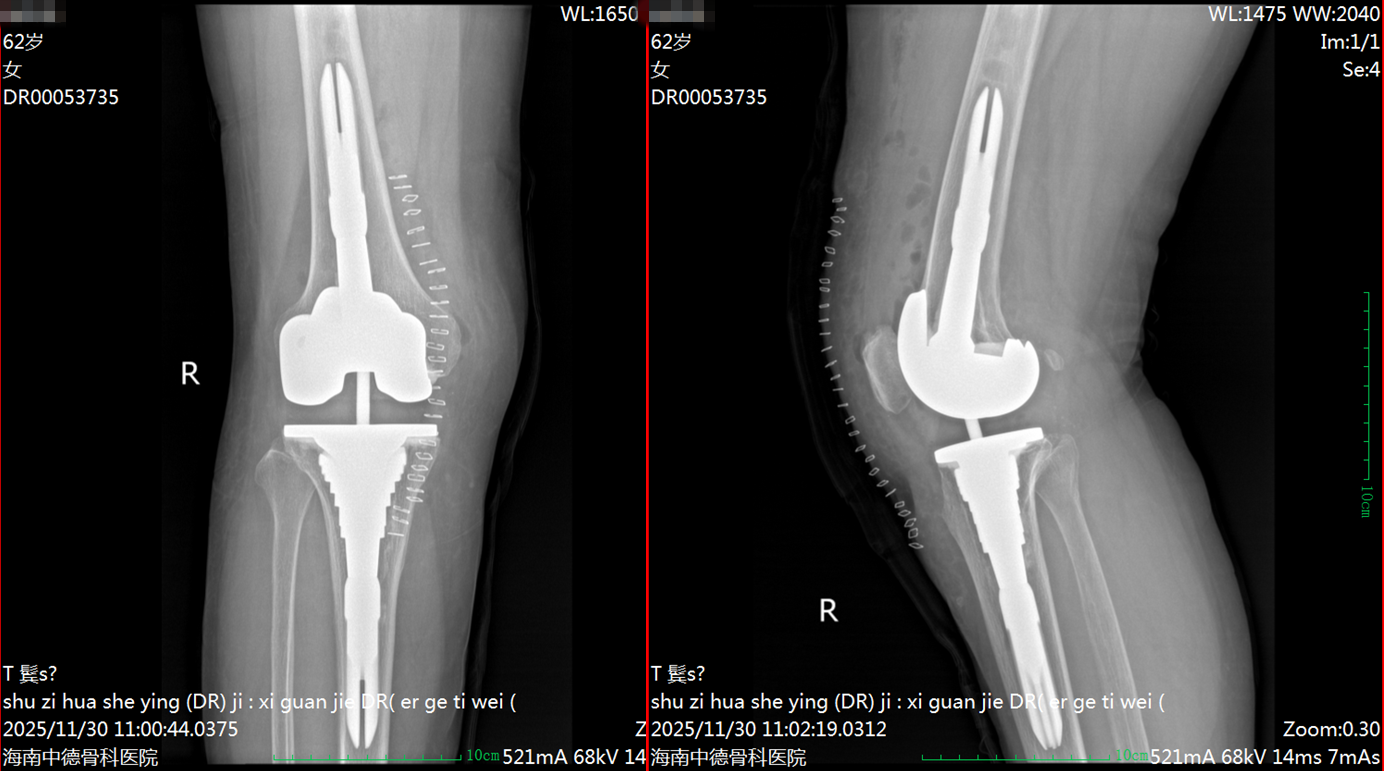

手术由付昆教授与张先龙教授共同主刀。术中,面对初次手术后形成的瘢痕粘连以及牢固的骨水泥固定,手术团队展现了精湛的技术。为尽可能保留患者宝贵的骨量,减少因取出原假体造成的骨缺损,付昆教授特意协调引进了先进的超声刀设备。该设备能精准、微创地清除固定假体的骨水泥,为后续重建奠定了良好的骨基础。同时,为确保翻修效果,医院还专门从广州调用了先进的翻修假体MBT袖套系统以满足手术需求。

在两位教授与手术团队的紧密配合下,手术过程顺利,原有假体被成功取出,并植入了新的翻修假体。该手术的圆满完成,体现了多学科协作及借助国内顶尖专家资源解决复杂骨科难题的优势。